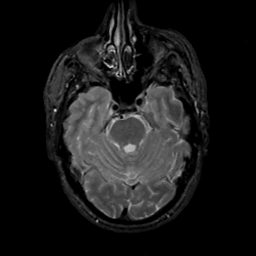

MR Study #14, June 2, 1991 -- Slice #15